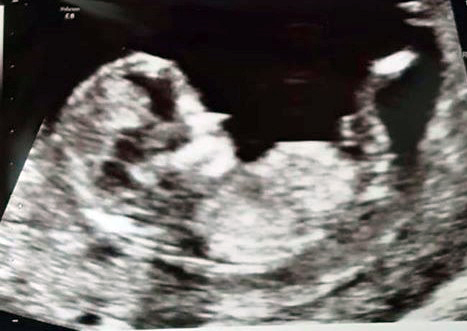

Hi, Are these images showing nubs, I can't be sure of what I'm looking at which line is the nub? Can anyone give a guess of gender? Thanks so much in advance.

The nub is that "y" shape coming from baby's bottom.

It's the same thing, just doesn't capture the Y shape. It's still pointing downward, though. It can still rise and be a boy, but I guess girl.